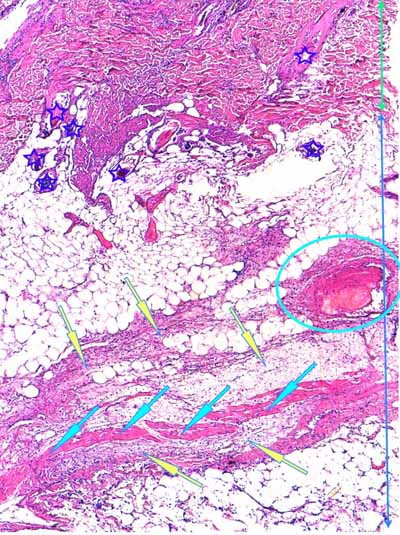

Photo 9 (Hémalun-Eosine X200) : une artériole hypodermique de moyen calibre

montre une vacuolisation de ses cellules endothéliales et un épaississement

de sa media et de son adventive. Sa lumière abrite un fragment de

thrombus fibrineux. L’hypoderme environnant est œdémateux.

Légendes de la Photo 9 :

- Flèches jaunes : vésiculation de l’espace sous-endothélilae et des cellules endothéliales

- Flèches turquoises : œdème et infiltrat neutrophilique dilacérant les adipocytes des lobules adipeux de l’hypoderme

- Pointe de flèche turquoise : adipocyte

- Ovale rouge pointillé : artériole de moyen calibre

- Ronds verts : endothélium de l’artériole

- Ronds noirs : media de l’artériole

- Ronds bleus : adventice de l’artériole

- Double flèche bleue : hypoderme

- Étoile rouge : thrombus fibrineux ostruant la lumière de l’artériole